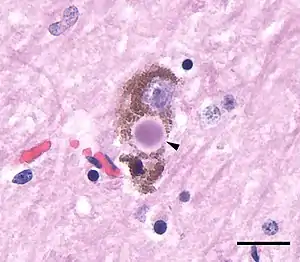

| Microscopic image of a Lewy body (arrowhead) in a neuron of the substantia nigra; scale bar=20 microns (0.02mm) | |